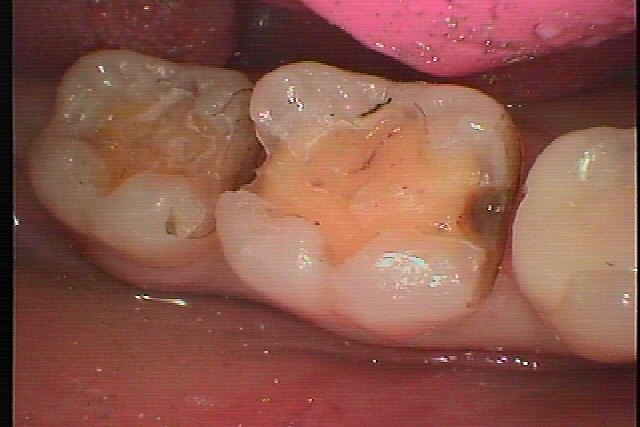

右下6,7番の銀歯をはずしていきます 銀歯をはずして虫歯治療からの白いセラミック治療へ|お知らせ |広島市安佐南区の歯科医院 右下6,7番の銀歯をはずしていきます 銀歯をはずして虫歯治療からの白いセラミック治療へ トップ お知らせ・ブログ お知らせ 右下6,7番の銀歯をはずしていきます 銀歯をはずして虫歯治療からの白いセラミック治療へ 右下6,7番の銀歯をはずしていきます 銀歯をはずして虫歯治療からの白いセラミック治療へ 右下7番になります このように銀歯が入っています 6,7番の銀歯をはずしていきました 少し虫歯になっていました 虫歯を除去していきました CR樹脂にて覆罩を行い型取りを行っています このようにきれいにセレックセラミックにて修復しています Web診療予約 初めての方へ 選ばれ続ける理由 院内設備について 歯が痛いしみる一般歯科 歯がぐらぐらする歯周病 健康な歯を保ちたい予防歯科 子供の虫歯予防をしたい小児歯科 銀歯をセラミックに審美歯科 白い歯を目指しませんか?ホワイトニング 矯正専門医がいるので安心矯正歯科 抜けた歯を補いたいインプラント・入れ歯 医院案内 スタッフ紹介 メリィハウス歯科クリニックオフィシャルホームページ ラベンダー歯科クリニックオフィシャルホームページ お知らせ・ブログ ホーム 診療科目 一般歯科 歯周病治療 予防治療 小児歯科 審美治療 ホワイトニング 矯正歯科 入れ歯・インプラント マウスピース矯正 初めての方へ 院長・スタッフ 設備紹介 医院案内・アクセス メニューを閉じる